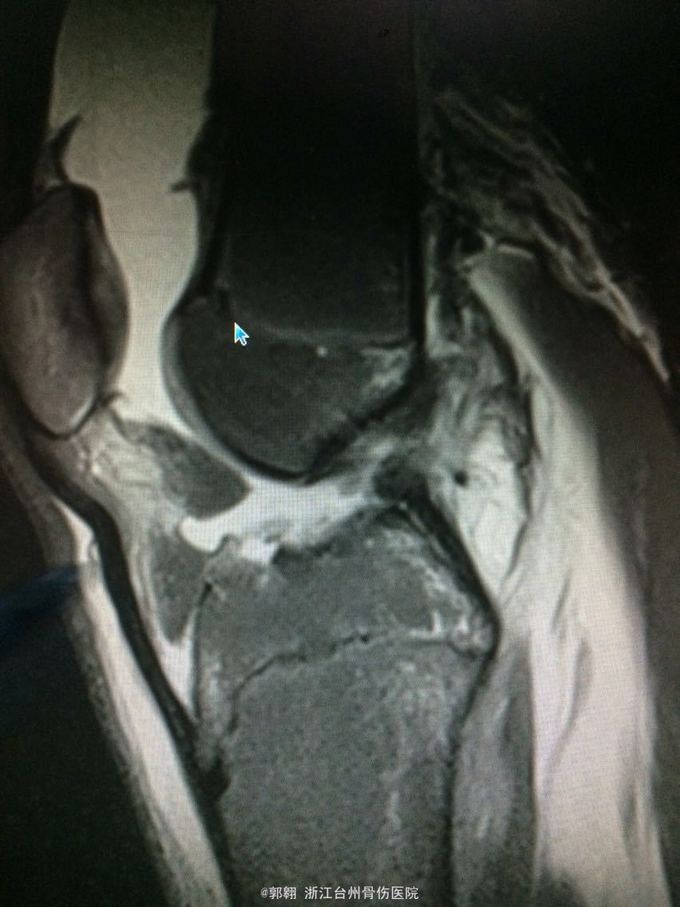

右膝关节跑步摔伤疼痛功能障碍3小时 病史:患者15岁 上体育课时跑步摔倒致右膝关节畸形疼痛 功能障碍,由老师送至医院就诊。

查体:右膝关节及小腿上段肿胀明显,张力较大,压痛位于内侧副韧带股骨处和膝关节外侧,膝关节波动感,浮髌试验阳性、扳膝试验阳性、抽屉试验阳性、Lachman阳性、膝关节屈伸活动因疼痛而障碍,足背动脉波动良好。 MRI:右膝关节股骨内髁骨折 胫骨平台外侧缘骨折

诊断:右膝关节内侧副韧带撕裂 前交叉韧带损伤 股骨内侧髁骨折胫骨平台外侧缘骨折 腓肠肌肌肉拉伤 处理:制动 支具托固定 冰敷 退肿止血药物治疗